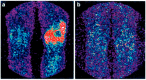

Background: Molecular nuclear medicine plays a pivotal role for diagnosis in a preclinical phase, in genetically susceptible patients, for radio-guided surgery, for disease relapse evaluation, and for therapy decision-making and follow-up. This is possible thanks to the development of new radiopharmaceuticals to target specific biomarkers of infection, inflammation and tumour immunology.

Methods: In this review, we describe the use of specific radiopharmaceuticals for infectious and inflammatory diseases with the aim of fast and accurate diagnosis and treatment follow-up. Furthermore, we focus on specific oncological indications with an emphasis on tumour immunology and visualizing the tumour environment.

Results: Molecular nuclear medicine imaging techniques get a foothold in the diagnosis of a variety of infectious and inflammatory diseases, such as bacterial and fungal infections, rheumatoid arthritis, and large vessel vasculitis, but also for treatment response in cancer immunotherapy.